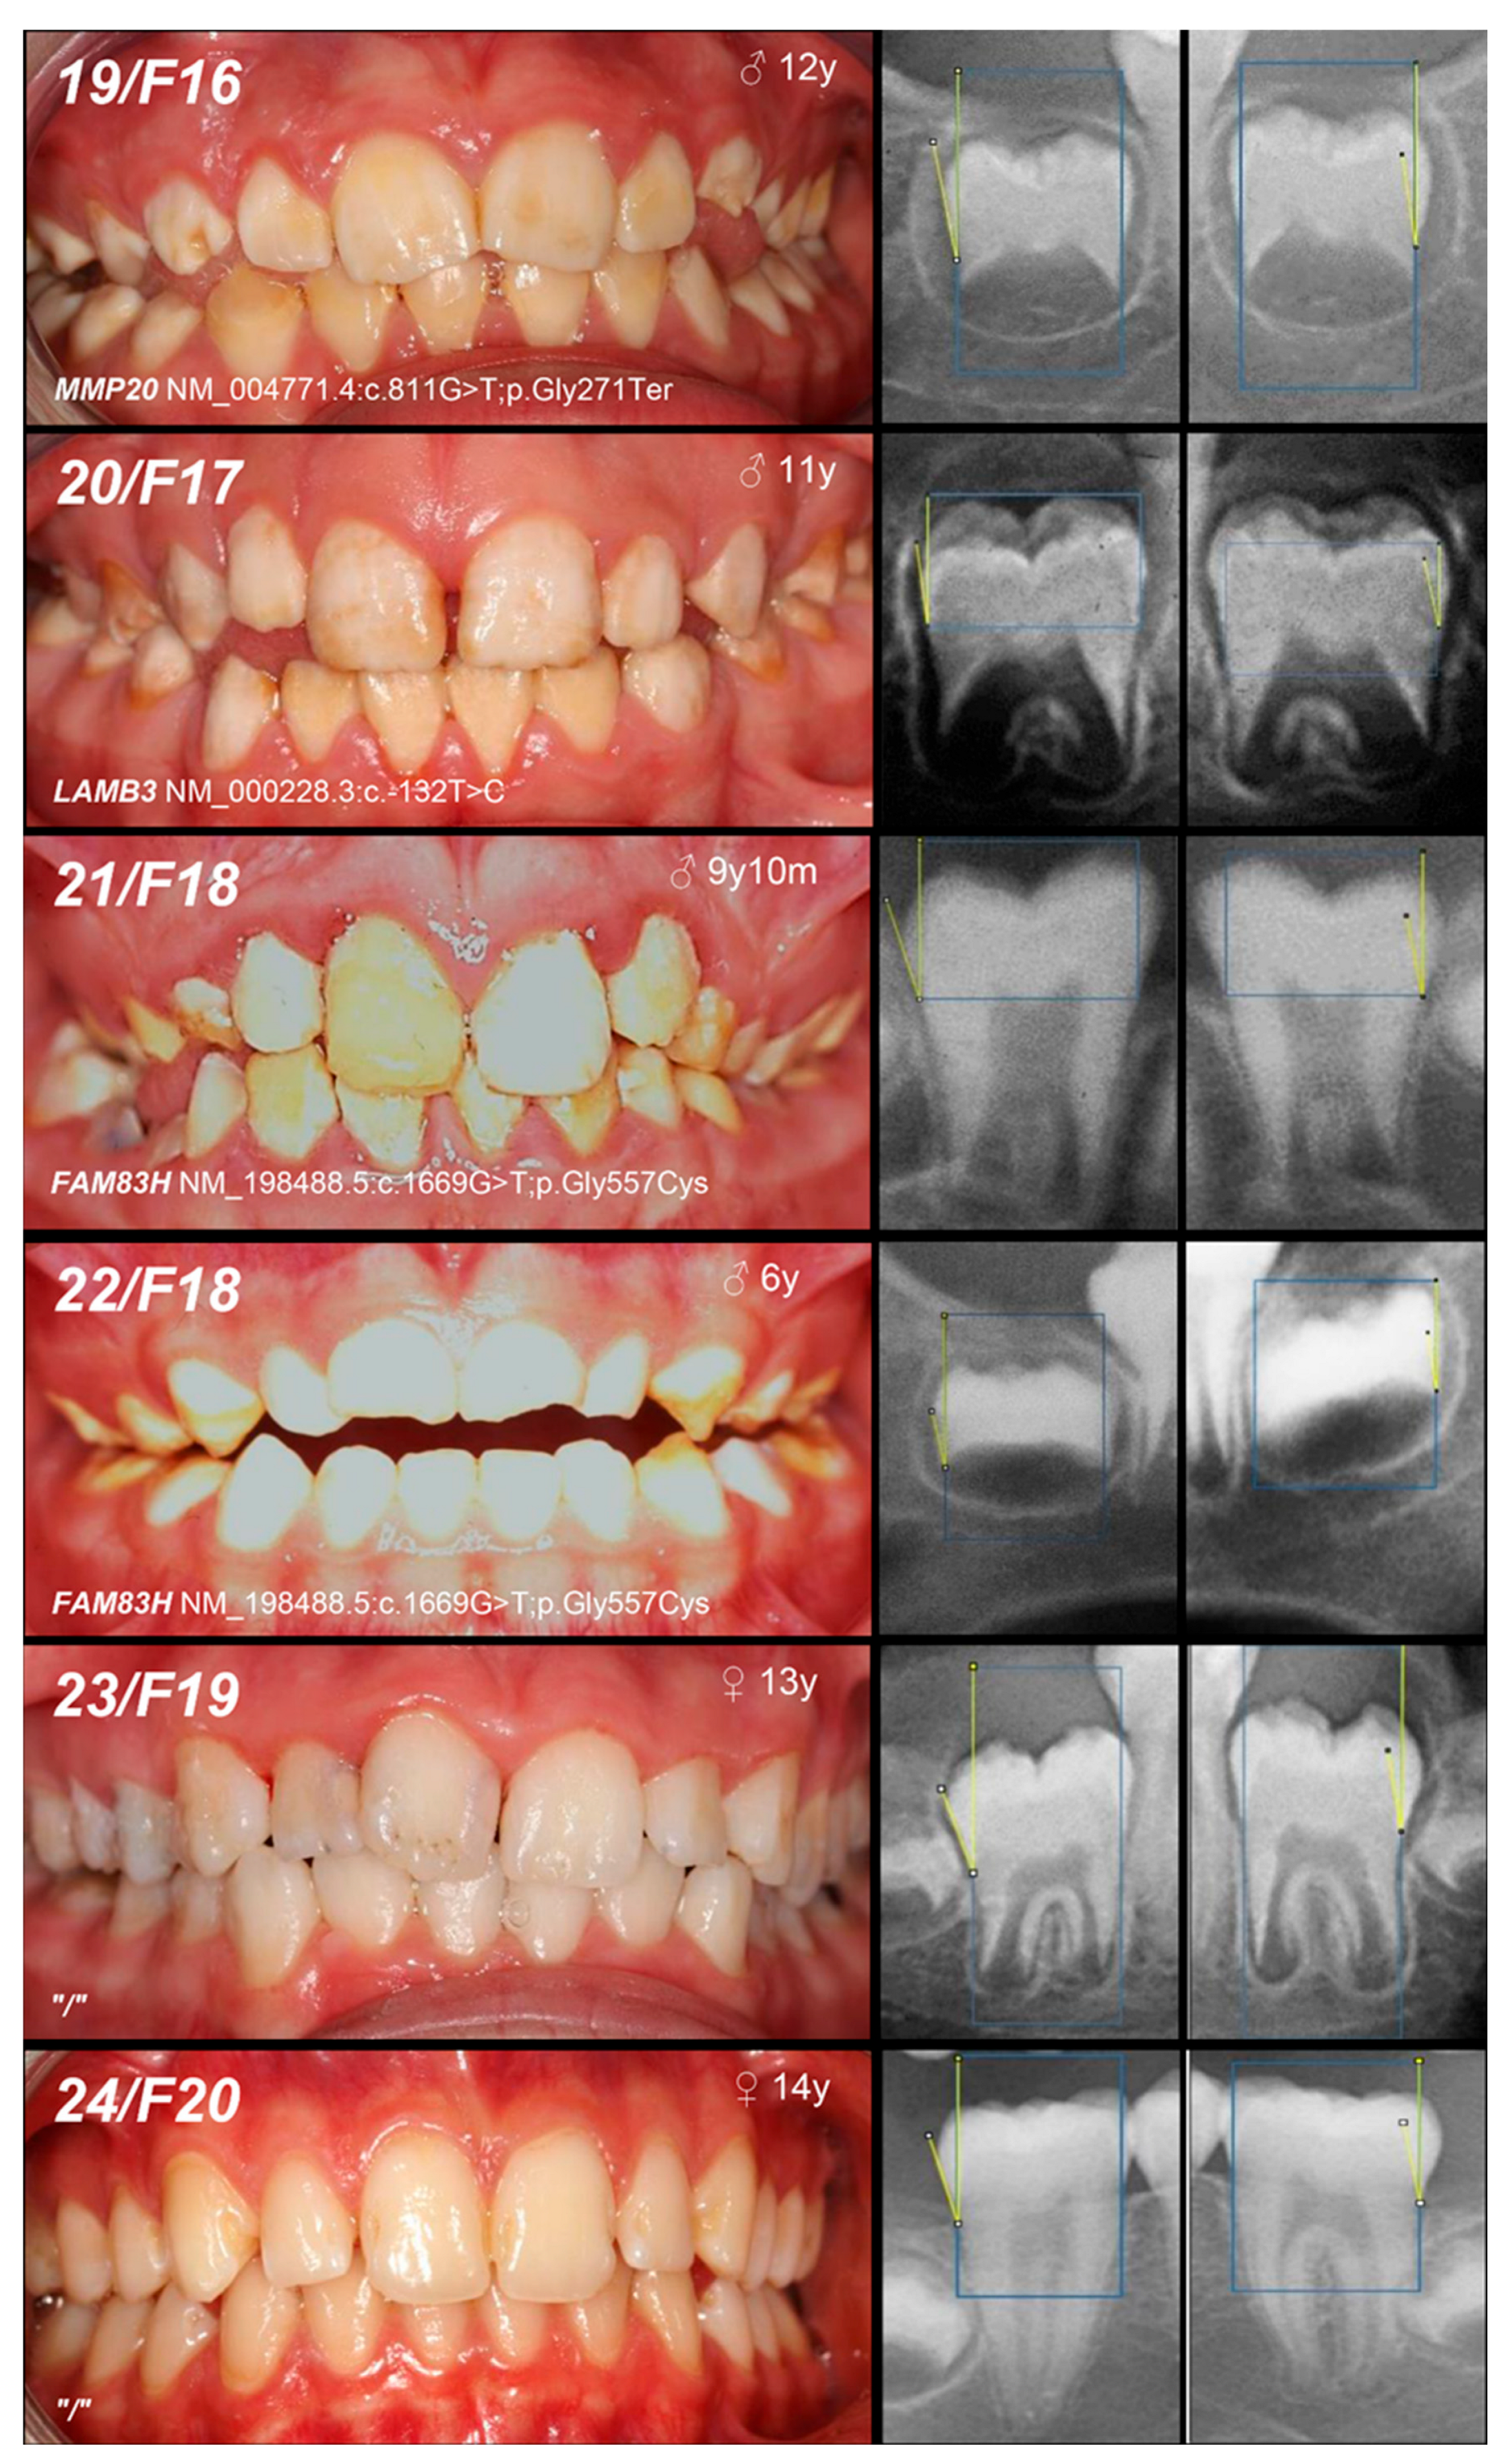

| 10, 11, F9 | Hypomineralized (heterogeneity) | IE, XLD, AMELX | c.103-3T>C | +/− | p.? | [26] | Mo(U) Fa (AC) | likely pathogenic (PP1:strong, PM2:moderate)* |

| 12, F10 | +/− | Mo (AC) Fa (NA) | ||||||

| and IIIA, AD, FAM83H | c.2363G>A | +/− | p.Ser788Asn | [26] | benign (BA1:stand-alone, BS2:strong, BP4:supporting, BP6:strong) | |||

| 13, F11 | Hypoplastic (heterogeneity) | IE, XLD, AMELX | c.485delT | 0/− | p.Phe162SerfsTer13 | novel | MoS (A) Fa (NA) | likely pathogenic (PVS1:very strong, PM2:moderate) |

| 14, F12 | Hypomineralized (pigmented hypomature) | IIA2, AR, MMP20 | c.389C>T | −/− | p.Thr130Ile | [27] | MoFa (UC) | likely pathogenic (PP5: strong, PM2: moderate) GnomAD: 0.001747 |

| 15, F13 | +/− | Mo (U) Fa (NA) | ||||||

| and c.446G>A | +/− | and p.Trp149Ter | novel | likely pathogenic (PVS1:very strong, PM2:moderate) GnomAD: 0.00000398 |

| 16, F14 | Hypomineralized (pigmented hypomature) | IIA2, AR, MMP20 | c.540T>A | +/− | p.Tyr180Ter | [28] | Mo (UC) Fa (U) | likely pathogenic (PVS1: very strong, PM2: moderate) GnomAD: 0.00000707 |

| 17, 18, F15 | c.811G>T | +/− | p.Gly271Ter | novel | Mo (AC) Fa (U) | likely pathogenic (PVS1: very strong, PM2: moderate) | ||

| +/− | ||||||||

| 19, F16 | +/− | Mo (UC) Fa (U) | ||||||

| 20, F17 | Hypoplastic (pitted) | IA, AD, LAMB3 | c.-132T>C | +/− | / | novel | Mo (AC) Fa (U) | VUS (PM2: moderate, BP7: supporting) |

| 21, 22, F18 | Hypomineralized (hypocalcified) | IIIA, AD, FAM83H | c.1669G>T | +/− | p.Gly557Cys | [29] | MoFa (NA) | benign (BA1: stand-alone, BS1: strong, BS2: supporting, BP4: supporting, BP6: supporting) * |

| +/− |